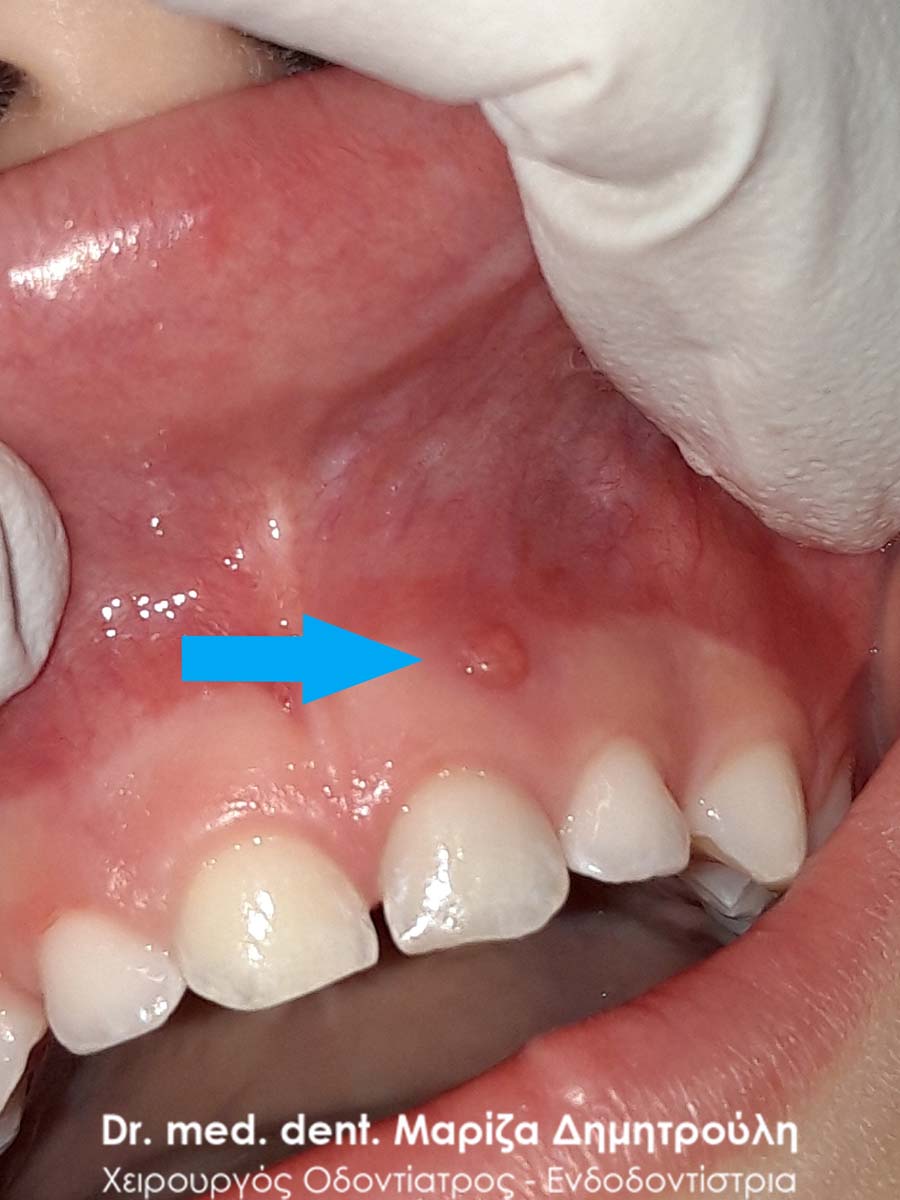

Επίσης στην πρόσθια περιοχή της άνω γνάθου παρατηρήθηκε ένα μικρό συρίγγιο στην περιοχή του πρώτου αριστερού νεογιλού γομφίου, ο οποίος είχε έντονη κινητικότητα χωρίς όμως να “πέφτει”. Στην περίπτωση αυτή ήταν απαραίτητη η εξαγωγή του νεογιλού δοντιού, γιατί το παιδί είχε το συρίγγιο τουλάχιστον τις τελευταίες 3 εβδομάδες (σύμφωνα πάντα με τα λεγόμενα της μητέρας). Με την εξαγωγή του δοντιού το συρίγγιο υποχώρησε τις επόμενες μέρες και το παιδί ανακουφίστηκε.

Συρίγγιο στην περιοχή του πρώτου νεογιλού τομέα